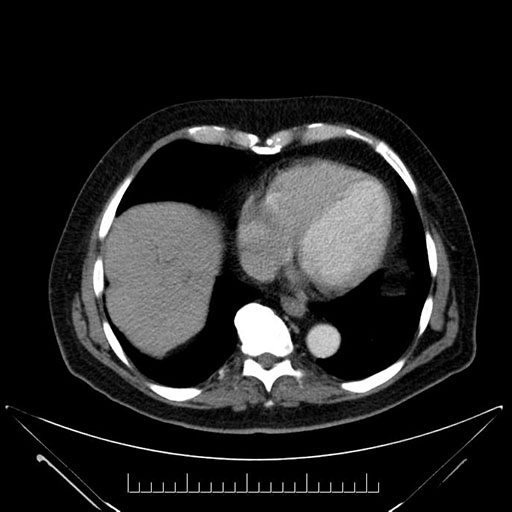

Imaging Analysis

Look through the patient's CT scan to identify any areas of concern for the necessary procedure.

Based on your CT findings, which issue(s) would give reason for "planned slowing down moment(s)" in this case?